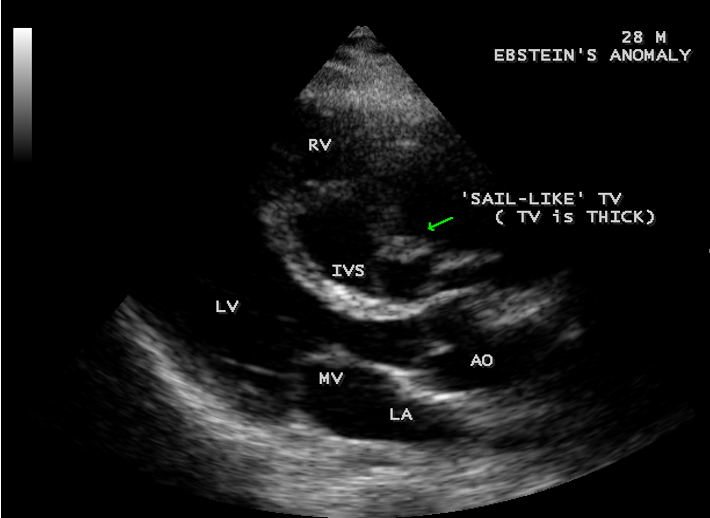

Case 4 (28-year old male with Ebstein’s anomaly)

A 28-year old male presented with cyanosis and auscultation revealed a ‘sail sound’ ( loud tricuspid component of first heart sound due to increased tension developed by the large anterior leaflet as it reaches the limits of its systolic excursion- an important sign of anterior leaflet mobility), a ‘cadence’ quality of quadruple rhythm due to wide splitting of first and second sounds ( due to complete right bundle branch block), atrial and ventricular filling sounds (summation of these sounds due to prolonged PR interval). ECG revealed the features of Ebstein’s anomaly as shown in Figures 11 and 12. X-ray chest revealed the Ebstein’s configuration as shown in Figure 13. 2D echocardiography revealed a ‘sail-like’anterior tricuspid leaflet forming a ‘muscular curtain’ in between the inflow and trabecular parts of the right ventricle as an ‘imperforate membrane’ with a ‘pinhole’communication, associated with a muscular VSD (ventricular septal defect) in the proximal, atrialized compartment of right ventricle suggesting an ‘atretic” (‘imperforate’) Ebstein’s anomaly as shown in Figures 14 to 27.

When chordae are absent, the free leaflets insert directly into the ventricular wall. In some cases, the greater part of the affected leaflets is firmly adherent to the right ventricular wall, drape the apical trabeculations and completely blended with ventricular wall. The communication between the atrialized and functional right ventricle is confined to slits or perforations in the anterior leaflet as Ebstein originally described. When the anteromedial commissure is fused and the anterior leaflet is intact, the tricuspid orifice is “imperforate” [30] and it occurs in 10% of hearts with Ebstein’s anomaly. In ‘imperforate Ebstein’s anomaly”, the septal, inferior and antero-superior leaflets may fuse either completely or in part, so that the inner surface of the inflow part of the right ventricle is formed by a “blanket” of dysplastic valve tissue towards the apex. The leaflets are said to be “plastered” out of the right ventricular myocardium, so that the fibrous transformation of the leaflets from the muscular precursors remain incomplete. . In severe cases, the leaflets are thickened, focally muscularized and attached to the underlying myocardium by numerous muscular stumps. In extreme cases, the fusion of leaflet tissue is so complete as a membrane-like continuum and the only identified remnants of leaflet tissue are nodular fibrous ridges at the level of the displaced functional annulus. In this setting, the entire inflow tract is atrialized and the functional right ventricle consists only of trabecular and outflow (infundibulum) components. The designation of “atretic“ Ebstein’s malformation was documented by Kumar [31] to the imperforate fused tricuspid valve and its incidence becomes even higher to 29% with an inclusion of “pinhole” communication {32}.

The anterior tricuspid leaflet is not involved in the process of downward displacement, it may be abnormally inserted occasionally and Shiina, et al documented the apical displacement of anterior tricuspid leaflet in 14% of cases echocardiographically [39]. The anterior leaflet forms a large, sail-like intracavitary curtain as in Figures 14, 25 and contains muscular strands instead of consisting entirely of a fibrous membrane as in the normal tricuspid valve [40]. It is potentially mobile with a brisk sail-like movement as shown in Figure 21 to 24 [41], free bloating with a ‘whipping motion’ across the right ventricular outflow tract (RVOT) as shown in Figure 26 and in some cases, the movement is restricted due to its adherence to the ventricular wall as in Figure 1 and 2, 4 and 9. It is often fenestrated, may in part be musculaized , inserting into the trabeculations of the right ventricle (RV) as in Figure 28 and rarely, the anterior leaflet forms an ‘atretic’ membrane that spans the midportion of the right ventricular cavity as in Figure 16.

Valvuloplasty It is favoured if the anterior leaflet is suitable for use as a functional monocuspid valve. The leaflet must exhibit adequate excursion and be free of large fenestrations. If the leaflet is ‘sail-like’ and free and when the tricuspid annulus is markedly dilated, an aggressive “Kay annuloplasty” is preferred as for case 4.

Ebstein’s original case was an example of obstruction at the tricuspid orifice by a membrane dividing the right ventricle into two halves as shown in Figure 16 of a 28-year old cyanotic male with ECG and X-ray characteristics as in Figure 11 to 13. suggesting an advanced spectrum of Ebstein’s malformation , necessitating RV exclusion techniques such as Starnes’ procedure. The florid case of Ebstein’s anomaly with the insertion of leaflet tissue along with ventricular walls as a ‘blanket’ as in Figures 28 and 29 in a 30-year old cyanotic male may go for an initial palliation with bidirectional Glenn shunt (cavopulmonary anastomosis). The other variants of moderate degree of leaflet tethering with varying degrees of regurgitation, but an intact basal leaflet attachments with atrioventricular junction as in Cases 1 and 2 may need a definite repair. In Ebstein’s mitral valve as in Figure 32 in a 10-year old boy, the downward displacement of functional annulus > 0.8 cm/m2 is not particularly striking and tends to affect the septal leaflet (anterior mitral leaflet) alone. The valve is thickened and mildly regurgitant due to rheumatic involvement rather than an anatomic cause.